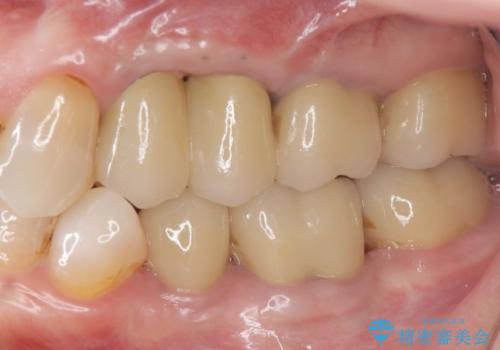

[ 深い虫歯・根管治療・セラミッククラウン ]複合した問題を持った虫歯治療

![[ 深い虫歯・根管治療・セラミッククラウン ]複合した問題を持った虫歯治療の症例 治療前](https://seimitsushinbi.jp/wp/wp-content/uploads/2022/09/b464b4c5c3053a5fc84212fb664a039f-500x350.jpg?v=1663667230)

![[ 深い虫歯・根管治療・セラミッククラウン ]複合した問題を持った虫歯治療の症例 治療後](https://seimitsushinbi.jp/wp/wp-content/uploads/2022/09/bd017e5dbd742f9bb33f09d39c8f1b52-500x350.jpg?v=1663667487)